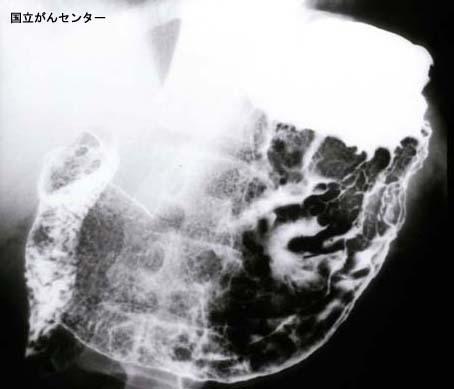

A case of gastric malignant lymphoma resembling type 4 gastric cancer.

Tokyo Pref., Cooperative study between National Cancer Center and Kyushu Cancer Center

Malignant Lymphoma/Malignant lymphoma

Stomach/More than one of above

X-ray

Type 4 Diffusely infiltrating type/

40 -

serosa (adventitia)